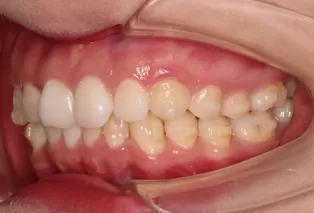

Intraoral photos